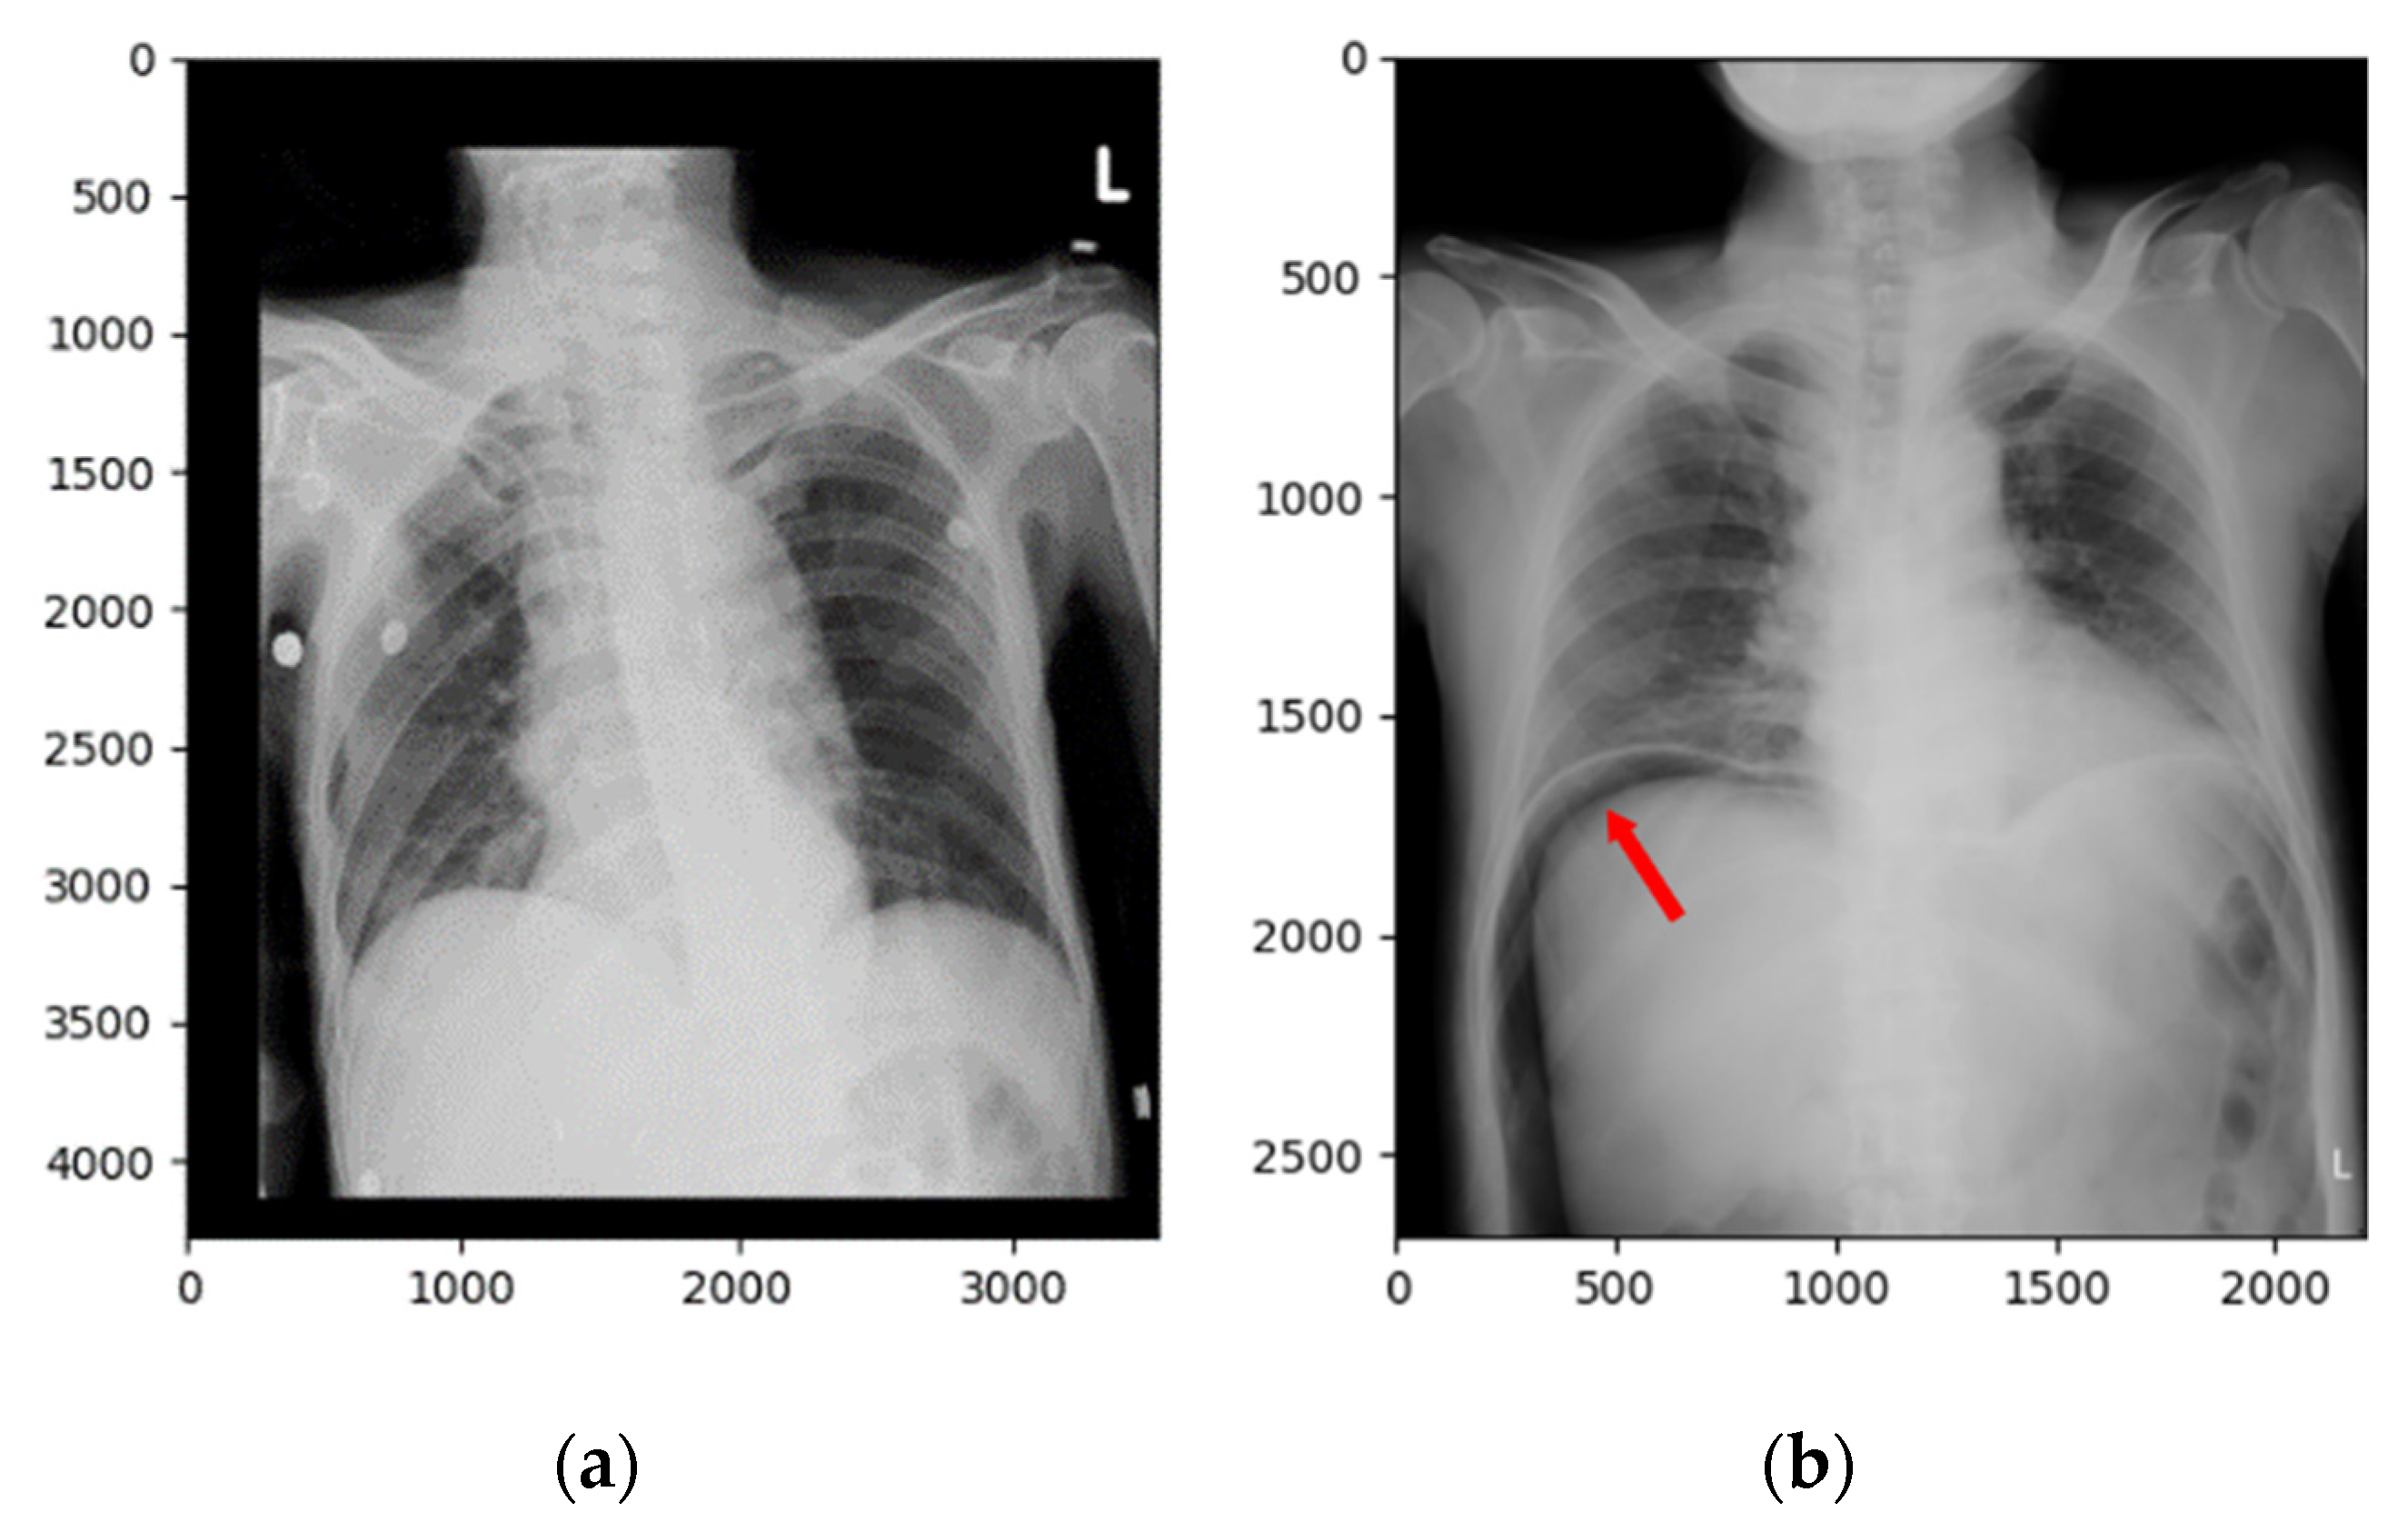

In addition to the quantity, the diversity of the data is another key. If the training dataset does not contain the rare cases of a particular symptom, the learned model will not recognize them. To explain this phenomenon, Figure 9 demonstrates the images of two examples of FN cases. Because most of the positive images in the training dataset have the free air under the diaphragm, which is considered as the representative feature of pneumoperitoneum, our trained model tended to use it to determine whether it has the symptom. Obviously, the raw CT images shown in Figure 9a,b do not contain subphrenic free air so that the trained CNN model could not identify them as positive. Similarly, Figure 10 demonstrates the images of the two FN cases. These images have characteristics similar to subphrenic free air under the right diaphragm, which makes the classifier misjudged them as positive. Therefore, in order to build a reliable pneumoperitoneum alarm system in the future, it is necessary to collect more training materials that contain images of diverse symptoms for model training.

Figure 10. The raw X-ray images and the corresponding heatmaps of two FP cases (a,b). The deep model detected the “fake” dome signs that were caused by its contrast to intraluminal, rather than extraluminal, air of the gastrointestinal tract.